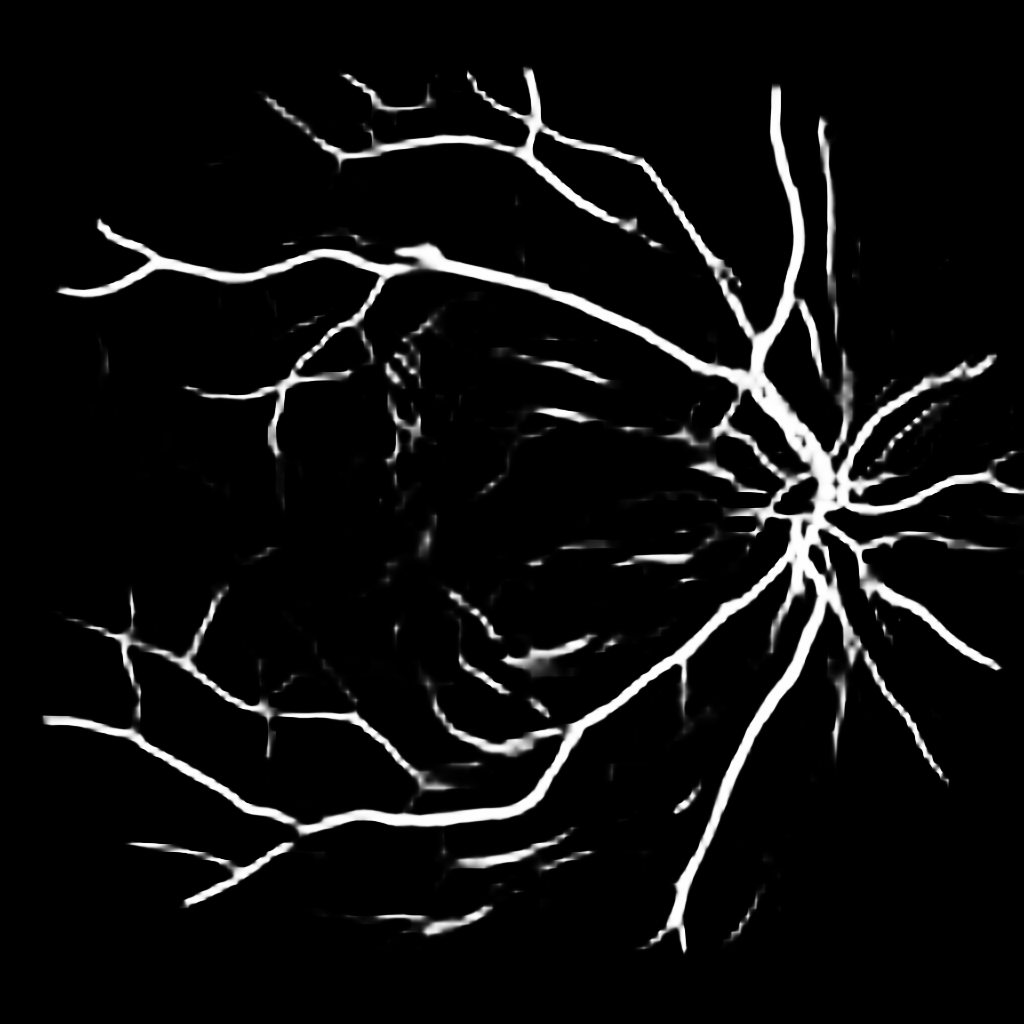

For completeness, and to test the robustness of our method, the models were also tested with several images sourced from Google™. We purposefully sourced extremely poor quality images (i.e. images with low contrast, speckle artefacts, etc), as well as images of pathological cases (i.e. Exdudates, Hemorrhages, etc). As there are no ground truth labels, only a qualitative assessment can be made of the results shown in Figure 2. In all cases, the models have accurately segmented the vessel structure whilst ignoring imaging artifacts and pathological lesions. This is very evident in the case of (5) and (6) where no vessels were segmented in areas of severe hemorrhaging.

{L to R: (1) Healthy, (2) Unhealthy, (3) Speckle Artefacts, (4) NPDR, (5) PDR, (6) Hemorrhages}